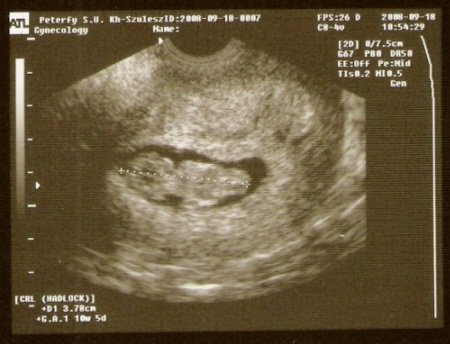

Grat a kis 1,5 cm-hez, illetve már a 22,5 mm-shez. .

Zsu: grat. a 8 mm-s kis csöpphöz. De már azóta tuti sokat nőtt.

Tici: én is a Tamarára szavazok. Nekem az jobban tetszik. Mi volt az uh-n?